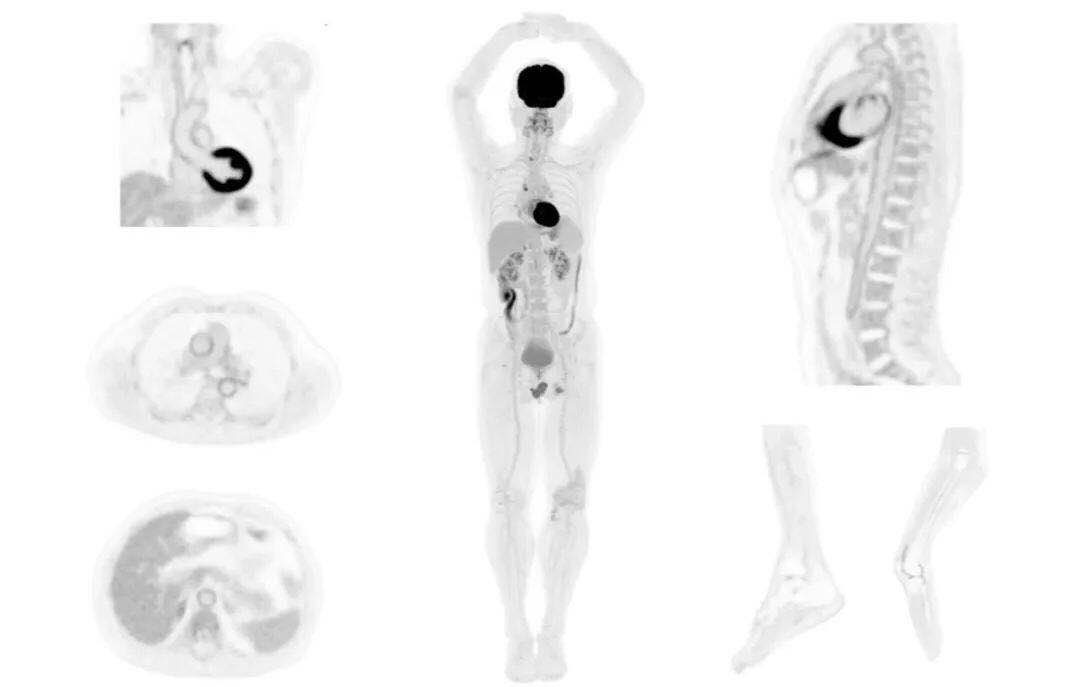

uExplorer探索者不再局限于傳統(tǒng)靜態(tài)代謝過程3D成像,而是在此基礎(chǔ)上新增一個維度——時間,從而實現(xiàn)4D全景成像。

注射總劑量為7.8mCi,14分鐘全身采集時間,在擁有超高靈敏度與超高分辨率的uEXPLORER上,即可得到展示顯示人體諸多精細結(jié)構(gòu)的高清三維圖像。

注射總劑量為7.8mCi,注射后1.6小時,基于uEXPLORER探索者掃描1分鐘的圖像

注射總劑量為0.67 mCi FDG(低于常規(guī)劑量的十分之一),基于uEXPLORER探索者掃描15分鐘的圖像

注射總劑量為6.9mCi,注射后10小時,基于uEXPLORER探索者掃描14分鐘的圖像